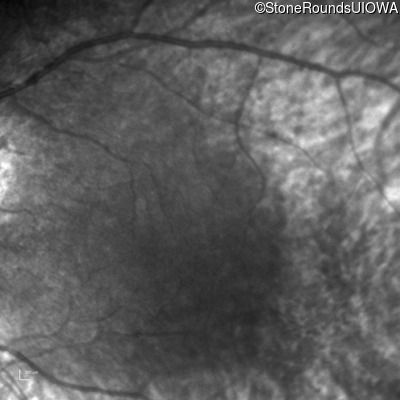

Infrared Fundus Photograph - Right -

No Light Perception

Exemplar

Expanded OCT Stack

×